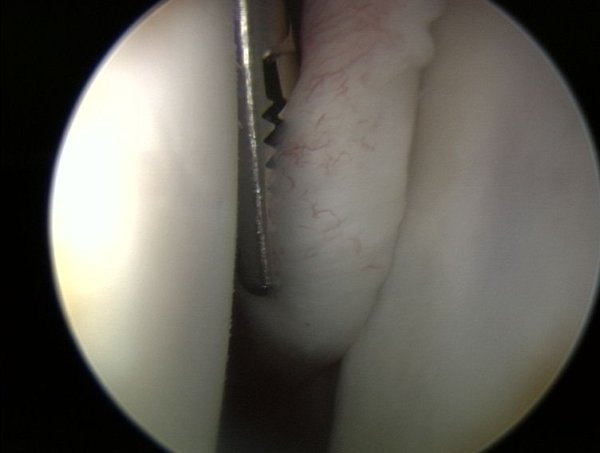

Tutaj jest widoczny obrąbek panewki w tylnej dolnej cześci ( lewa reka ) : " opona ".

Tutaj widoczny jest obrąbek stawowy z panewką ( patrzymy od tyłu na przednią cześć panewki) bez zmian, z lewej główka kości ramiennej.

Z prawej strony jest widoczny brak obrąbka stawowego na panewce, jedynie w górnej cześci jest jeszcze rozpoznawalny. Z lewej strony widoczna jest głowa kości ramiennej.

" Naciąganie opony " czyli umieszczenie obrąbka na panewce w anatomicznej pozycji. Przyczepianie obrąbka odbywa się przy pomocy tzw. kotwiczki, ktorą może być z metalu lub biowchłanialna.

Tutaj widoczny jest ten sam region, po artroskopowej rekonstrukcji obrąbka.